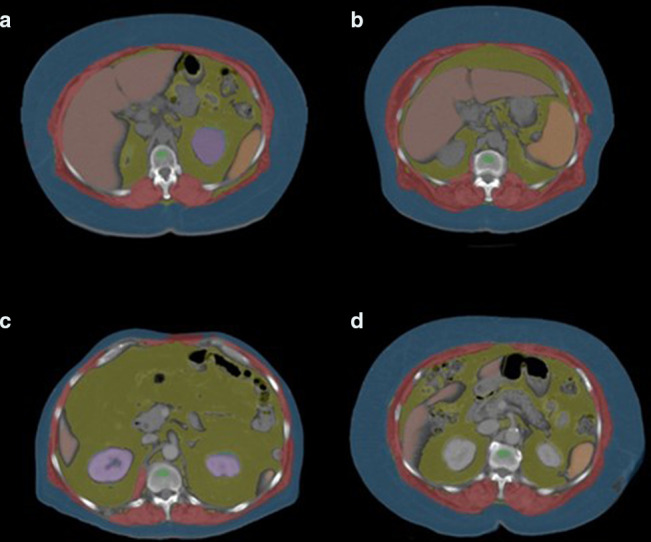

Methods: In this retrospective age- and sex-matched case-control study, 9029 total patients underwent initial abdominal CT for a variety of indications over a 20-year interval at one institution. 3535 case patients (mean age at initial CT, 66.5 ± 9.6 years; 63.4% female) who went on to fall (mean interval to fall, 6.5 years) and 5494 controls (mean age at initial CT, 66.7 ± 9.8 years; 63.4% females; mean follow-up interval, 6.6 years) were included. Falls were identified by electronic health record review. Validated and fully automated quantitative CT algorithms for skeletal muscle, adipose tissue, and trabecular bone attenuation at the level of L1 were applied to all scans. Uni- and multivariate assessment included hazard ratios (HRs) and area under the receiver operating characteristic (AUROC) curve.

Abstract Image